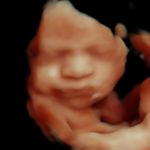

4D/5D/HD Ultrasound Gallery

Gallery